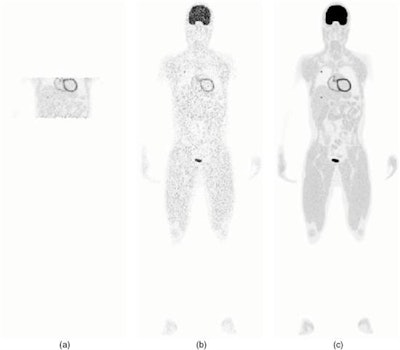

Reconstructed images from three scan protocols. (a) Four block-ring single-bed scan; (b) Four block-ring multi-bed whole-body scan; (c) the EXPLORER total-body scan.CRC-STD curves showed that with resolution modeling, all three protocols achieved a similar maximum CRC. EXPLORER, however, provided a 6.9-fold reduction in the background standard deviation (27.9%) compared with four block-ring multibed imaging (192%), and a two-fold reduction compared with single-bed imaging (57.3%).